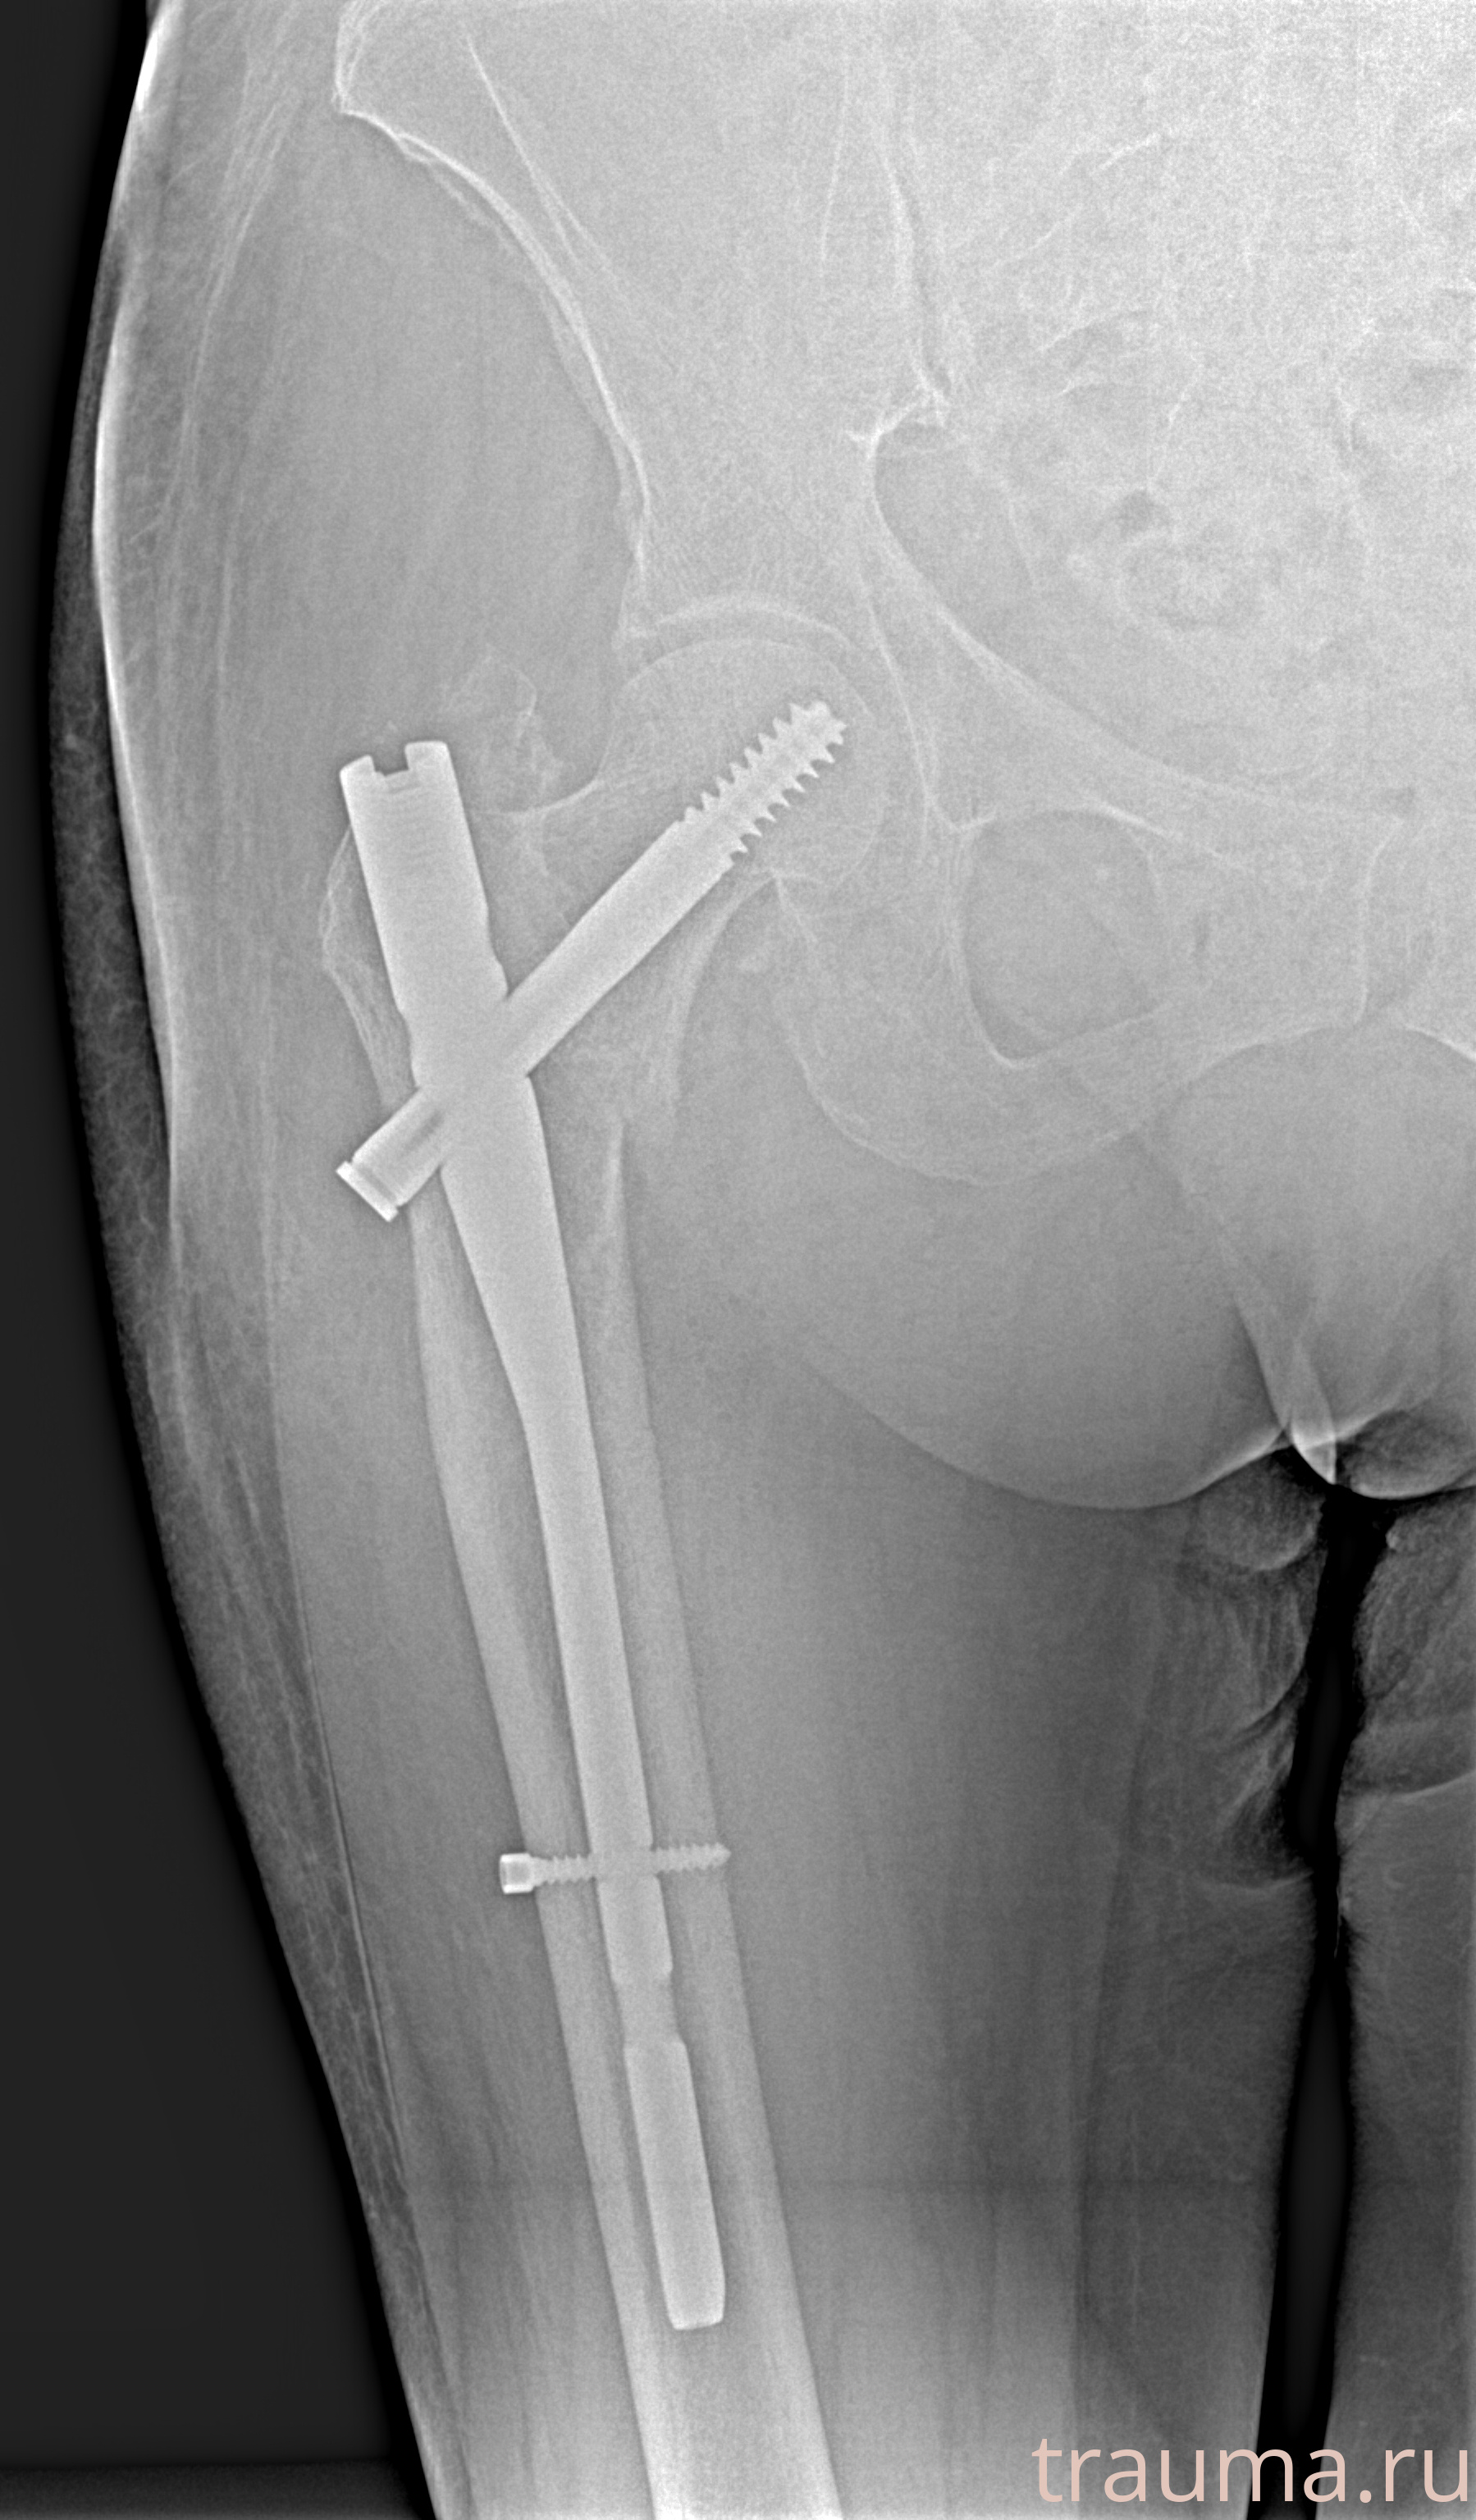

Рентгенограммы

Рентген на дому: по вашему адресу приезжает врач-рентгенолог, травматолог-ортопед с мобильным рентгеновским аппаратом, проводит диагностику травмы или заболевания, делает необходимые рентгенограммы, дает рекомендации по дальнейшему лечению. Получить качественные снимки в домашних условиях возможно благодаря уникальной методике, разработанной МосРентген Центром для института  Склифосовского